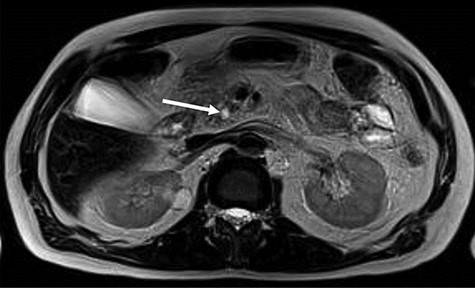

EUS, 15 days after, suggested chronic inflammation of the pancreas with multiple stones (≤9.0 mm) in the main pancreatic duct leading to ascending dilatation and tortuosity of the main pancreatic duct. Moreover, it presents a solid formation in the head/uncinate transition on its dorsal face (Fig. 2). A biopsy was performed and the cytologic result was inconclusive.

EUS—solid formation in the head/uncinate transition on its dorsal face. (A) EUS demonstrating multiple calculi and the pancreatic head; (B) EUS with evidence of a 7-mm Wirsung duct (PCR = pancreas; W=Wirsung duct). (C) Fine needle aspiration (FNA) of the nodular lesion.